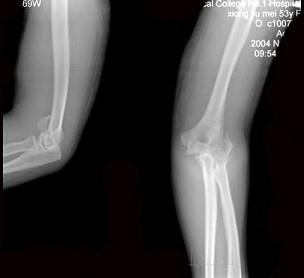

问题 53岁女性患者,因摔倒时手掌着地,感右肘关节肿痛、畸形,X线摄片如图所示,下列正确的诊断是 ( )

选项 A、右肱骨小头骨骺分离 B、右肱骨内髁骨折 C、右肱骨内上髁骨折 D、右肱骨外上髁骨折 E、右肱骨外髁骨折

答案 D